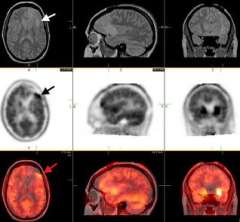

PET: The upper panel images are MRI scans showing a small low-grade astrocytoma in the left frontal lobe (white arrow). The middle panel shows a FDOPA-PET with high uptake (black arrow) in an area immediately in front of the abnormality seen on MRI. The lower panel shows the fused (overlapping) MRI and PET images. At surgery, the area identified by PET revealed the diagnostic tissue.

Positron Emission Tomography (PET)

MRS: The upper right MRI shows an abnormal area in the right parietal lobe. A square "voxel" (marked by the arrow) is the area of interest within the tumor. The middle left MRS image shows the amount of choline (CHO) contained in each part of the brain. Areas of high CHO (arrow) suggest closer crowding of cells (such as a tumor). The lower left MRS shows that NAA (a chemical found in neurons, or brain cells) is low in the area of the tumor. Because tumor cells displace neurons, low NAA may also suggest tumor. In this case, a biopsy confirmed a low-grade astrocytoma.

MRI scans showing a small low-grade astrocytoma